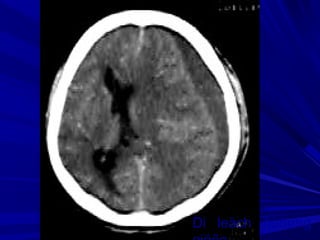

Phát hiện xuất huyếtPhát hiện xuất huyết

Xuất huyết là các vùng tăng đậm độ và có thể thấyXuất huyết là các vùng tăng đậm độ và có thể thấy

trong các bệnh lý:trong các bệnh lý:

Tụ máu ngoài màng cứng,Tụ máu ngoài màng cứng,

Tụ máu dưới màng cứngTụ máu dưới màng cứng

Xuất huyết màng nãoXuất huyết màng não

Xuất huyết não thấtXuất huyết não thất

Xuất huyết trong nãoXuất huyết trong não

Phân biệt hoá vôi và xuất huyết nhỏ vùng nhân nềnPhân biệt hoá vôi và xuất huyết nhỏ vùng nhân nền

Phân biệt xuất huyết cầu não với hình ảnh nhiễuPhân biệt xuất huyết cầu não với hình ảnh nhiễu